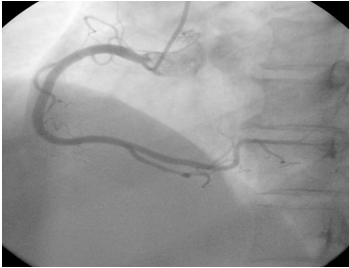

正常右冠状动脉造影